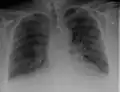

Kerley B lines in radiograph of acute cardiac decompensation. The short, horizontal lines can be found everywhere in the right lung.

Chronic stable heart failure may easily decompensate (fail to meet the body's metabolic needs). This most commonly results from a concurrent illness (such as myocardial infarction (a heart attack) or pneumonia), abnormal heart rhythms, uncontrolled hypertension, or a person's failure to maintain a fluid restriction, diet, or medication.[50]

Chest radiograph of a lung with distinct Kerley B lines, as well as an enlarged heart (as shown by an increased cardiothoracic ratio, cephalization of pulmonary veins, and minor pleural effusion as seen for example in the right horizontal fissure. Yet, no obvious lung edema is seen. Overall, this indicates intermediate severity (stage II) heart failure.

Chest X-rays are frequently used to aid in the diagnosis of CHF. In a person who is compensated, this may show cardiomegaly (visible enlargement of the heart), quantified as the cardiothoracic ratio (proportion of the heart size to the chest). In left ventricular failure, evidence may exist of vascular redistribution (upper lobe blood diversion or cephalization), Kerley lines, cuffing of the areas around the bronchi, and interstitial edema. Ultrasound of the lung may also detect Kerley lines.[73]